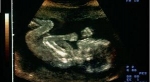

La importancia de el uso de la ecografía durante el embarazo es vital , ya que por medio de este método, podemos evidenciar el buen desarrollo de la gestación o detectar alguna anormalidad que se presente.

Se puede determinar el tiempo del embarazo ya sea midiendo la distancia del saco gestacional, el diámetro de la cabeza del feto (diámetro biparietal), longitud cráneo - rabadilla, longitud el hueso de la pierna (fémur), diámetro de la circunferencia abdominal y calcular mediante este último dato el peso fetal.

También establece la posición del feto, permite el diagnóstico y control de los embarazos múltiples (gemelos, trillizos, etc.) y precisa con rapidez los embarazos gemelares después de la décima semana de gestación.  Detecta alteraciones desde el principio del embarazo (aborto diferido, huevo huero, embarazos fuera del útero), permite  identificar malformaciones y sirve de ayuda excelente en el estudio del líquido amniótico por punción.